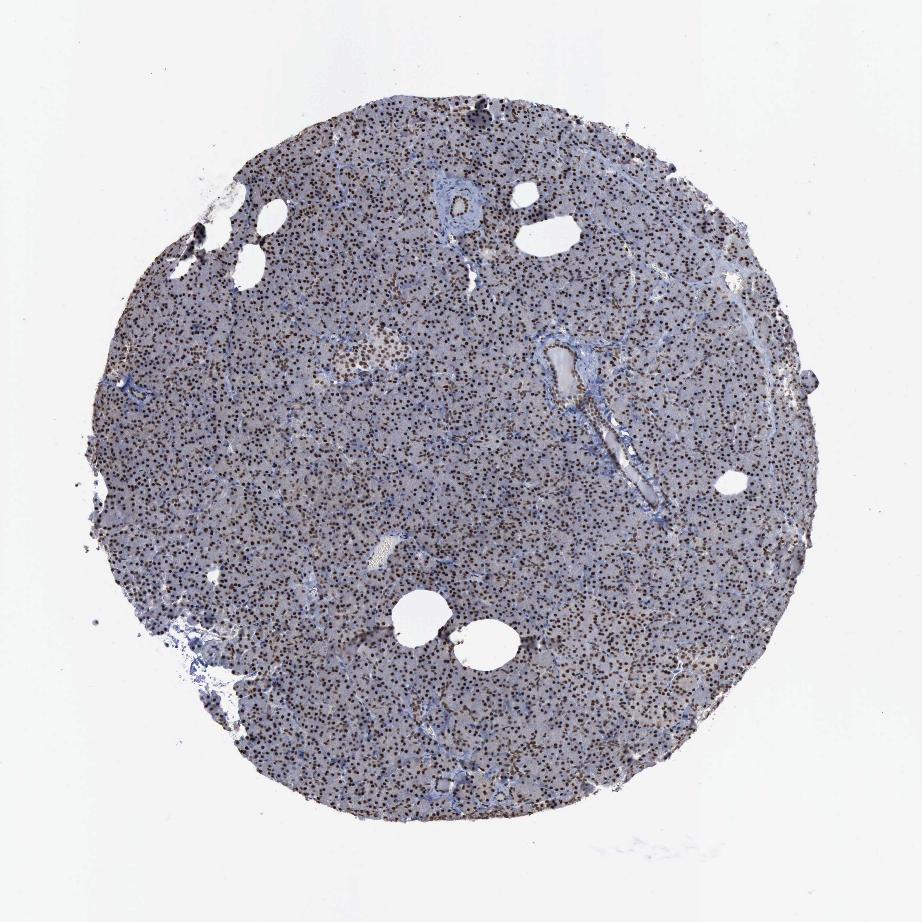

TISSUE PRIMARY DATA PANCREAS Show tissue menu

PANCREAS - Antibody stainingi

Antibody staining in the annotated cell types in the current human tissue is reported as not detected, low, medium, or high, based on conventional immunohistochemistry profiling in selected tissues. This score is based on the combination of the staining intensity and fraction of stained cells.

Each image is clickable and will lead to virtual microscopy that enables deeper exploration of all samples and also displays staining intensity scores, fraction scores and subcellular localization as well as patient and tissue information for each sample.

Antibody HPA030521Antibody HPA030522Antibody HPA030523Antibody CAB000148Antibody CAB080240Antibody CAB080241Antibody CAB080242

Exocrine glandular cells LowHighLowMediumHighHighHigh

Pancreatic endocrine cells LowMediumNot detectedLowNot detectedHighHigh